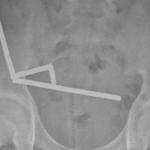

Преди време баща на три деца се подлага на операция за херния. Лекарите обаче установяват, че въпросната „херния“ е съставена от утроба с маточна шийка, фалопиева тръба и яйчник и е прикрепена към неспуснат тестис.

Хернията включва утроба с маточна шийка и фалопиева тръба и овариална тъкан. Те диагностицират пациента с рядък тип хермафродитизъм.

Екипът премахва цялата излишна структура без усложнения. Този тип хермафродитизъм се открива често единствено по случайност.

„Синдромът на персистиращ мюлеров канал е рядка форма на мъжки псевдо-хермафродитизъм, който се открива по случайност по време на хирургическа операция на крипторхизъм или ингвинална херния – пишат още специалистите – Овариалната тъкан се прикрепва здраво към тестиса и епидермиса, открива се и на други места и често наподобява тумор.“